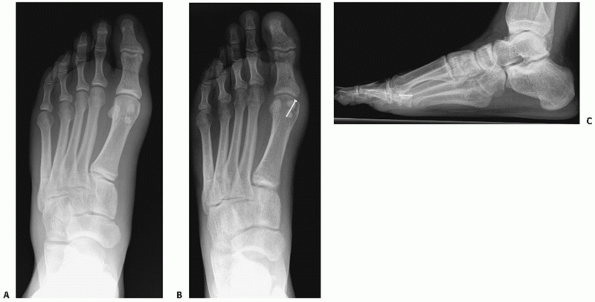

strength of individual ligaments across many of these joints. The

important characteristics to note are (a) the plantar ligaments are

significantly stronger than the dorsal ligaments, (b) the multiple

ligaments overlap among the joints of the lesser four tarsometatarsal

joints, and (c) the Lisfranc ligament, which is the largest and

strongest ligament of this joint complex, represents the only

ligamentous support between the medial leg and the middle and lateral

legs in the forefoot. The Lisfranc ligament originates from the plantar

lateral aspect of the medial cuneiform just below the plantar extent of

the second tarsometatarsal joint and inserts on the plantar and medial

aspect of the second metatarsal base. At best it is an indirect link

between the first and second metatarsals. There is no interligamentous

connection between the first and second metatarsal.

are important for management are stability and associated fracture

management. Extra-articular fractures, which appear with these

injuries, should be treated as described elsewhere in this text to

preserve that structure’s role in foot function. Intra-articular

fractures of the tarsometatarsal joints should be handled in the

context of the treatment of the joint complex.

with metatarsal motion, and tenderness to palpation but fail to exhibit

any instability should be considered a sprain. In addition to the

normal concept of rest, ice, compression, and elevation (RICE) for

treating sprains, the need for immobilization is important. These

injuries can be severely debilitating and require a long recovery

period.24,76

Nondisplaced ligamentous injuries with or without small plantar

avulsion fractures of the metatarsal or tarsal bones should be placed

in a well-molded short-leg walking cast (Table 60-5).

Initially, the patient is kept non-weight bearing with crutches and

only permitted to bear weight as comfort allows. Once full weight

bearing can be accomplished in a cast, the patient is tested for